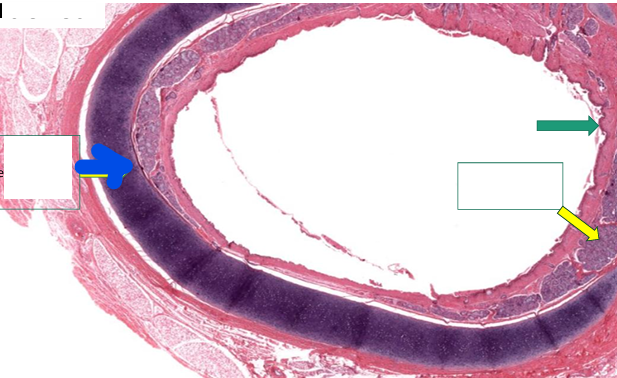

Trachea

(low power view)

Blue- Hyaline cartilage

Green- epithelium

Yellow- Glands in submucosa

1. Epithelium

2. Tracheal glands in submucosa

3. Elastic membrane

4. Perichondrium

5. Hyaline cartilage

6. Trachialis muscle

7. Adventitia